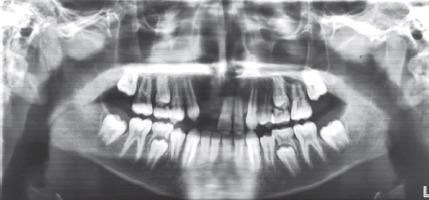

Tooth loss due to trauma often triggers residual alveolar resorption to a greater degree in the sagittal direction leading to atrophy. However, in a pediatric patient, if this defect is left untreated, it can cause further atrophy leading to collapse of the arch. In the maxillary anterior area, this is also of esthetic concern. Hence, it is viable to reconstruct the alveolar defects and restore the alveolar anatomy with superior quality of bone while the patient is still in growing phase to avoid any structural and dental malformation, as well as to provide a more novel treatment like dental implant at a later stage when growth ceases. Modes for successfully augmenting the bone are diverse. Among these, barrier membrane with guided bone regeneration, distraction osteogenesis, and bone block graft is ubiquitous. The current case report deals with the management of horizontal atrophic anterior maxillary region using autologous block bone graft harvested from mandibular symphysis, to augment the alveolar ridge and aid in esthetic and functional restoration of alveolar anatomy by restoring the defect with the bone of superior quality as well as preparing the site for receiving implant prosthesis in future when growth ceases. Bhandary M, Hegde AM, Shetty R, Augmentation of Narrow Anterior Alveolar Ridge Using Autogenous Block Onlay Graft in a Pediatric Patient: A Case Report. Int J Clin Pediatr Dent 2021;14(2):311-314.

因创伤导致的牙齿缺失通常会在矢状方向上更大程度地引发残余牙槽骨吸收,进而导致萎缩。然而,对于儿科患者,如果这种缺损不进行治疗,可能会导致进一步萎缩,进而导致牙弓塌陷。在上颌前部区域,这也涉及美观问题。因此,在患者仍处于生长阶段时,重建牙槽骨缺损并恢复具有优质骨的牙槽骨解剖结构是可行的,以避免任何结构和牙齿畸形,并在生长停止后的后期提供更新颖的治疗方法,如牙种植体。成功增加骨量(骨增量)的方式多种多样。其中,引导骨再生屏障膜、牵张成骨和骨块移植很常见。本病例报告涉及使用从下颌联合处获取的自体块状骨移植来处理上颌前部水平萎缩区域,以增加牙槽嵴,并通过用优质骨修复缺损以及为生长停止后未来接受种植修复体准备位点,来帮助牙槽骨解剖结构的美观和功能恢复。Bhandary M, Hegde AM, Shetty R, 儿科患者使用自体块状贴附移植增加狭窄前牙槽嵴:病例报告。《国际临床儿科牙科学杂志》2021年;14(2):311 - 314。